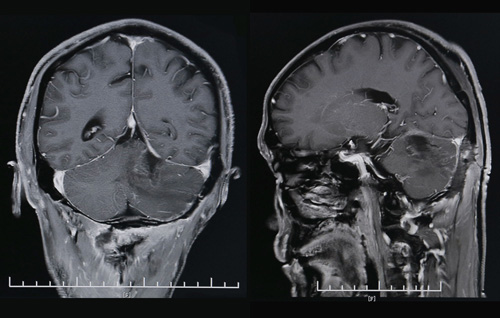

術后CT影像顯示,腫瘤已經(jīng)消失

這臺難度較高的手術由神經(jīng)外科主任沈建康教授親自操刀。從切開頭皮到止血縫合,總共歷時約4小時。“手術的關鍵是找到和完整切除血管性腫瘤。”沈建康教授解釋道,囊腫被穿刺后囊液流出,癟下去的囊腫就會使血管性腫瘤“隱身”于周圍腦組織中,若不加以徹底摘除,仍具有危害性。這對于手術醫(yī)師的技術和經(jīng)驗是極大的考驗。